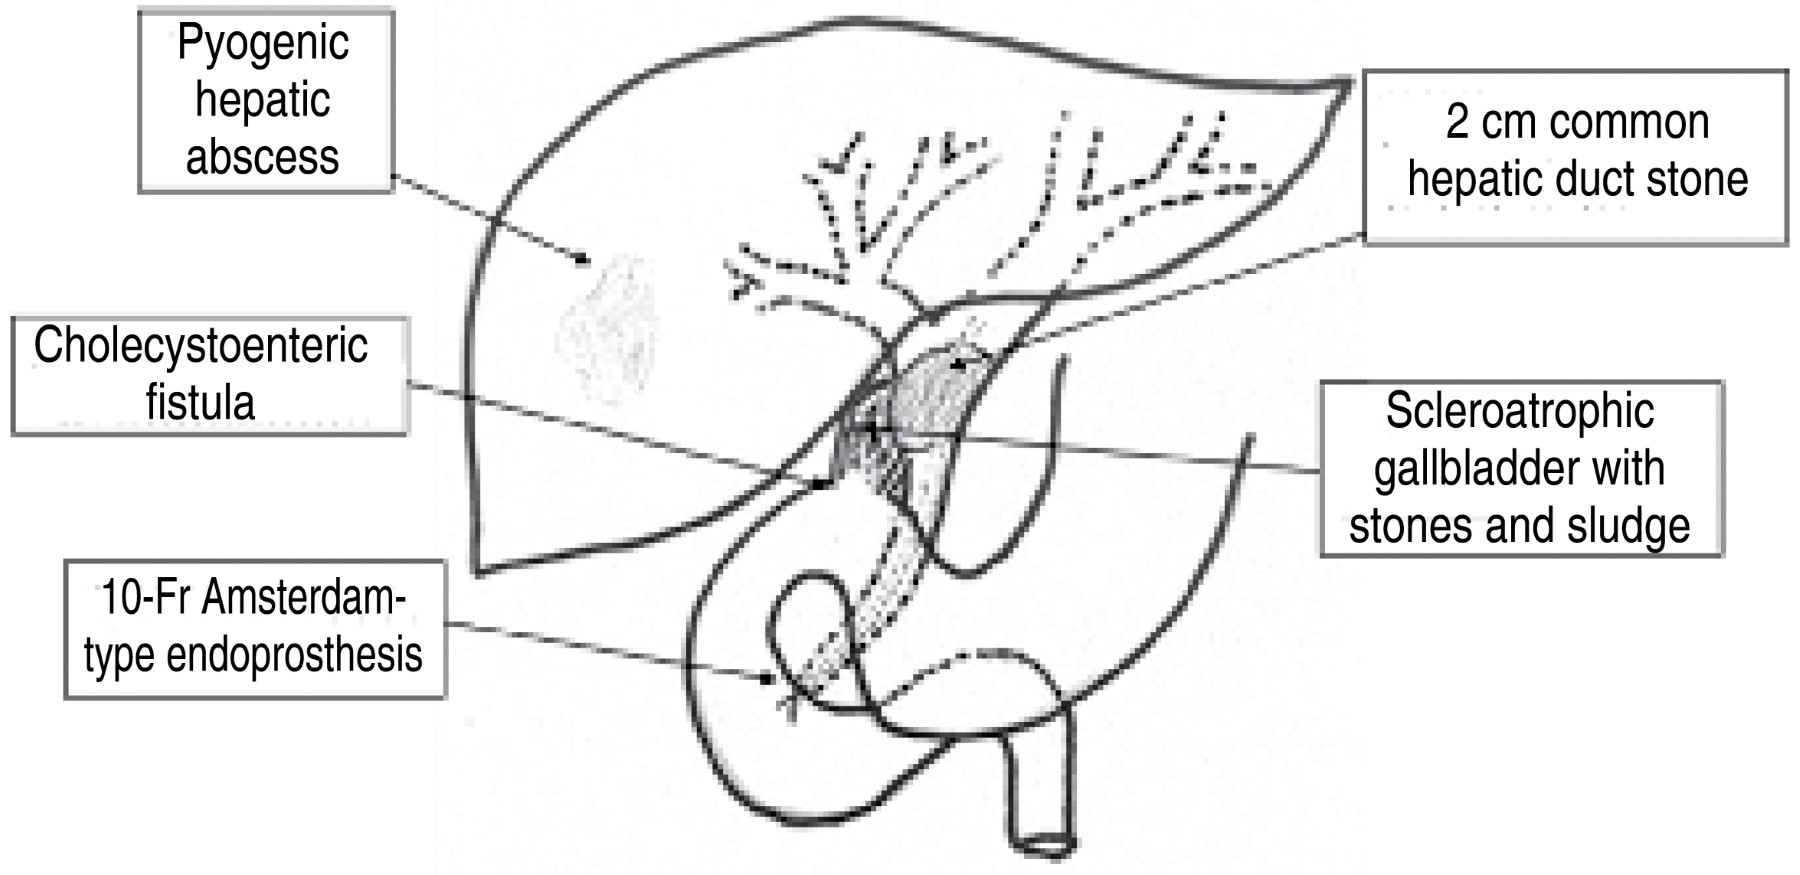

An abdominal CT scan was performed on 10/02/19, which reported findings of a hypodense image of 80 × 53 mm with 23 HU in segments VI and VII concerning liver abscess on the right side, hepatomegaly at the expense of the same lobe, presence of pneumobilia, which is observed in communication with the anterior wall of the gallbladder, little free fluid in the pelvic cavity, bilateral pleural effusion and passive atelectasis. Similarly, ERCP was requested on 10-09-19, which reported a common bile duct of 10 mm, a circular filling defect of approximately 20 mm, which delays emptying the contrast medium from the biliary tract, reporting probable Mirizzi syndrome type IV, and bilioenteric fistula of a site to be determined. Sphincterotomy is performed, sweeping with a lithotripsy cannula and placing a 10 × 10 cm Amsterdam-type stent (Figure 2).

A right subcostal incision was made with findings of cholecystobiliary fistulas to the common hepatic and cholecystoduodenal to the first portion (Figure 4).

When dissecting the plastron, the scleroatrophic gallbladder is opened over the palpated litho; the Amsterdam prosthesis is extracted from the interior of the main biliary tract, together with a 2 cm litho embedded in the common hepatic, resulting in a 2 cm defect involving the common hepatic and partially the left hepatic duct, A 3 mm fistulous orifice from the vesicular remnant to the duodenal knee, it was decided to close the cholecystoduodenal fistula with a 2-0 polypropylene loop and three separate polypropylene stitches on top of the loop, curative biliodigestive bypass from the jejunum to the common hepatic in a single mouth with the left hepatic (Hepp's technique) in "golf club" with separate stitches and 10 ml of fibrin sealant around the anastomosis, ending the jejunum-jejunal Roux-en-Y at 40 cm from the biliodigestive bypass in a transmesocolic way, fixing the jejunal loop to the mesocolon with separate 3-0 polypropylene stitches (Figure 5).